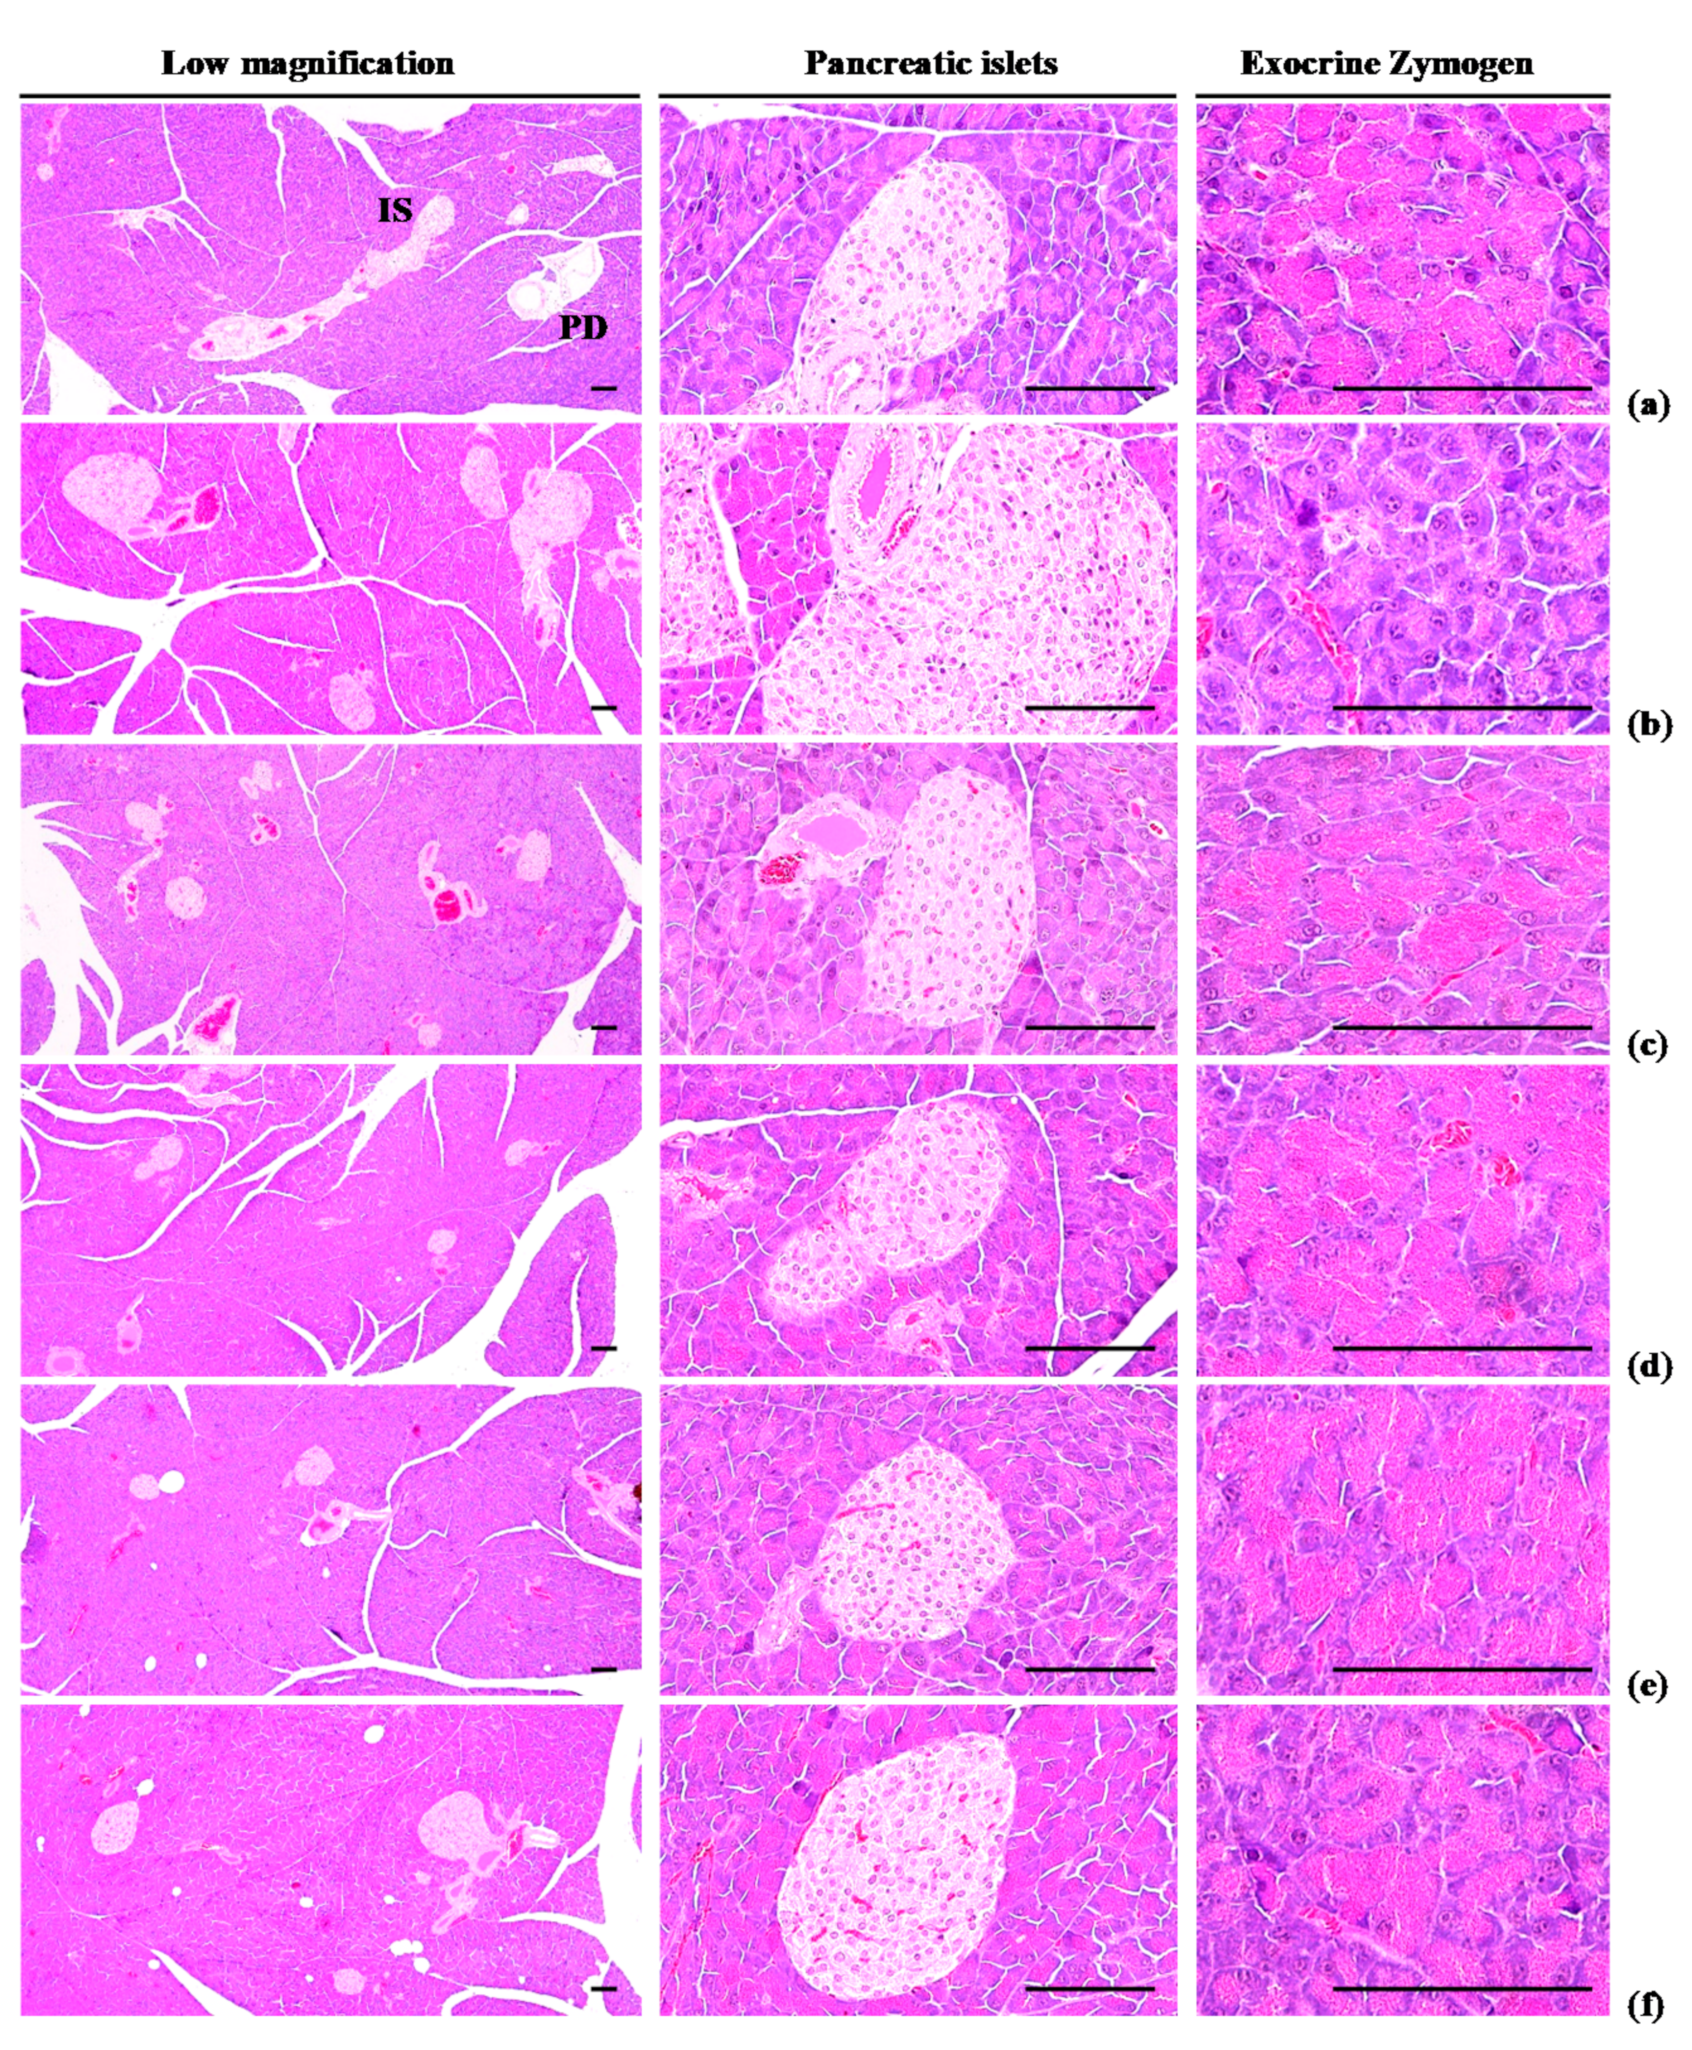

3.1.5. Effects of WL on Exocrine Pancreas Zymogen Granule Content

Exocrine pancreas zymogen granule content was less (p < 0.01) in HFD control group than in intact control group, due to the discharge of zymogen granules. However, exocrine pancreas zymogen granule content significantly (p < 0.01) increased in three WL dosage groups and the metformin group, compared with the results in HFD control group. In particular, 50 mg/kg WL and metformin inhibited the HFD-induced exocrine pancreas zymogen granule depletions at histopathological levels (Table 4; Figure 5). The proportion regions of exocrine pancreas filled by zymogen granule in HFD control group were decreased −78.08% as compared to intact control group, but they were increased 210.39, 309.07, 259.93, and 217.69% in metformin 250 mg/kg, WL 200, 100, and 50 mg/kg groups as compared to those of HFD control group.

Figure 5.

Representative general histological images of the pancreas, taken from NFD or HFD supplied mice. (a) Vehicle (distilled water) 10 mL/kg orally administered mice with NFD supply (Intact control); (b) Vehicle 10 mL/kg orally administered mice with HFD supply (HFD control); (c) 250 mg/kg of metformin oral administered mice with HFD supply (Metformin); (d) WL 200 mg/kg orally administered mice with HFD supply (WL200); (e) WL 100 mg/kg orally administered mice with HFD supply (WL100); (f) WL 50 mg/kg orally administered mice with HFD supply (WL50). NFD = Normal pellet diet; HFD = 45% Kcal high-fat diet; WL = Wasabi Leaf/Folium, Wasabia japonica (Miq.) Matsum extracts; IS = Pancreatic islet; PD = Pancreatic secretory duct. All Hematoxylin & Eosin stain. Scale bars = 80 µm.

3.2.3. Effects of WL on Pancreatic Islet Hyperplasia and Expansion

Pancreatic islet mean diameters and numbers were significantly (p < 0.01) higher observed in HFD control group than intact control group because of marked pancreatic islet hyperplasia or component endocrine cells. Hyperplasia and expansion of islets decreased in a significant and dose-dependent manner (p < 0.01) in response to metformin treatment and each of the three WL dosages, compared with the results in HFD control group. In particular, 50 mg/kg WL and metformin inhibited the HFD-induced hyperplasia and expansion of pancreatic islets (Table 7; Figure 5). The mean pancreatic islet numbers in HFD control group were increased 344.74% as compared to those of intact control group, but they were changed by −48.52, −71.01, −62.72, and −49.11% in metformin 250 mg/kg, WL 200, 100, and 50 mg/kg groups as compared to HFD control group. The proportions of islet filled regions in HFD control group were increased 117.85% as compared to intact control group, but they were decreased −43.60, −53.28, −48.47, and −43.90% in metformin 250 mg/kg, WL 200, 100, and 50 mg/kg groups as compared to HFD control group.

An increase in the deposit of adipose tissue is a general aspect of obesity [13,14,16,31]. Adipose tissue acts as an energy storage organ, as well as an endocrine and secretory organ [38]. Adipose tissue secretes adipokines; alterations in the action, expression, and secretion of adipokines in obese individuals may contribute to the development of various diseases, including insulin resistance [16,39]. In the present study, 84 days continuous oral treatment of all three dosages of WL 200, 100, and 50 mg/kg, dose-dependently and significantly inhibited the deposit of adipose tissues and adipocyte hypertrophy, and also by metformin 250 mg/kg. Especially, WL 50 mg/kg constantly showed favorable inhibitory activities against HFD-induced accumulation of adipose tissues and adipocyte hypertrophy as comparable to metformin group, at least in a condition of the present DEXA and histopathological analysis. These results are considered as obvious evidences that WL has favorable anti-obese activities in HFD mice, dose-dependently, and constantly as comparable to metformin 250 mg/kg, at dose level of 50 mg/kg (Table 2 and Table 3, Figure 2, Figure 3 and Figure 4). It is known that obese individuals develop a reduced number of zymogen granules, acinar cell atrophy, and pancreatic steatosis [14,16,31,40]. The increase of pancreatic zymogen granules in exocrine acinar cells implies the production of digestive enzymes, particularly for digestion of protein and lipid [41]. The diminishments of pancreatic zymogen granules were also detected in HFD control group as compared with intact control group at histopathological observation, and they caused lipid absorption related obesity. Though, the treatment of all three dosage of WL effectively inhibited the diminishments of zymogen depositions in exocrine pancreas, dose-dependently, and also by metformin 250 mg/kg. In particular, WL 50 mg/kg constantly showed affirmative inhibitory activities against HFD-induced exocrine pancreas zymogen granule, in the current study. These results are considered as evidences that WL has favorable anti-obese activities, might be through pancreatic enzyme production or release inhibitions in HFD supplied mice, dose-dependently, and constantly as comparable to metformin treatment, at dose of 50 mg/kg, at least in a condition of the present analysis (Table 4, Figure 5).